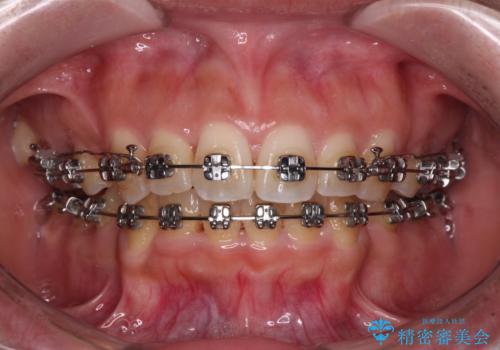

八重歯と上顎前突 ワイヤー装置での抜歯矯正

- メタルブラケット

- 3年3ヶ月

上下の前歯が接触する仕上がりとなったので、横顔の印象が大幅に改善されました。